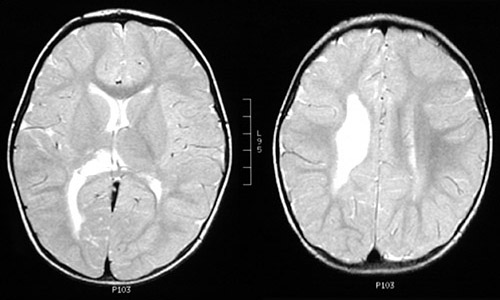

| The term "cerebral palsy" refers to a developmental disorder of motor function present from infancy or early childhood. This condition is probably the result of a vascular accident with localized infarction occurring prenatally or intrapartum. The actual event often goes unrecognized until a motor problem such as spastic diplegia or hemiplegia is noted early in development. In this case, the child was noted to have impaired motion, particularly of extensor muscles, on the left. This MRI scan reveals mild loss of white matter, basal ganglia, and thalamus on the right with resultant ex vacuo ventricular dilation. Cerebral palsy is non-progressive, and the childhood brain has an amazing ability to "rewire" itself, minimizing the deficit. |